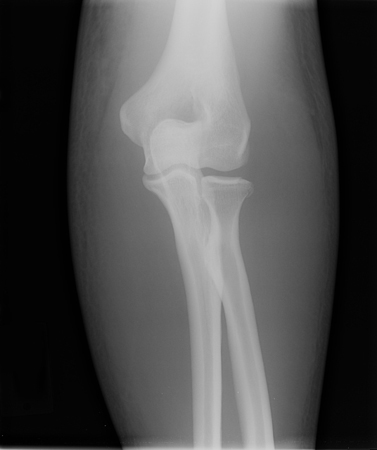

An anteroposterior (AP) and lateral plain film radiograph of the elbow should be obtained to ensure that the joint is concentrically reduced. [Figure caption and citation for the preceding image starts]: Anteroposterior x-ray view of a reduced elbow dislocationPersonal collection of Dr Paul Novakovich [Citation ends].